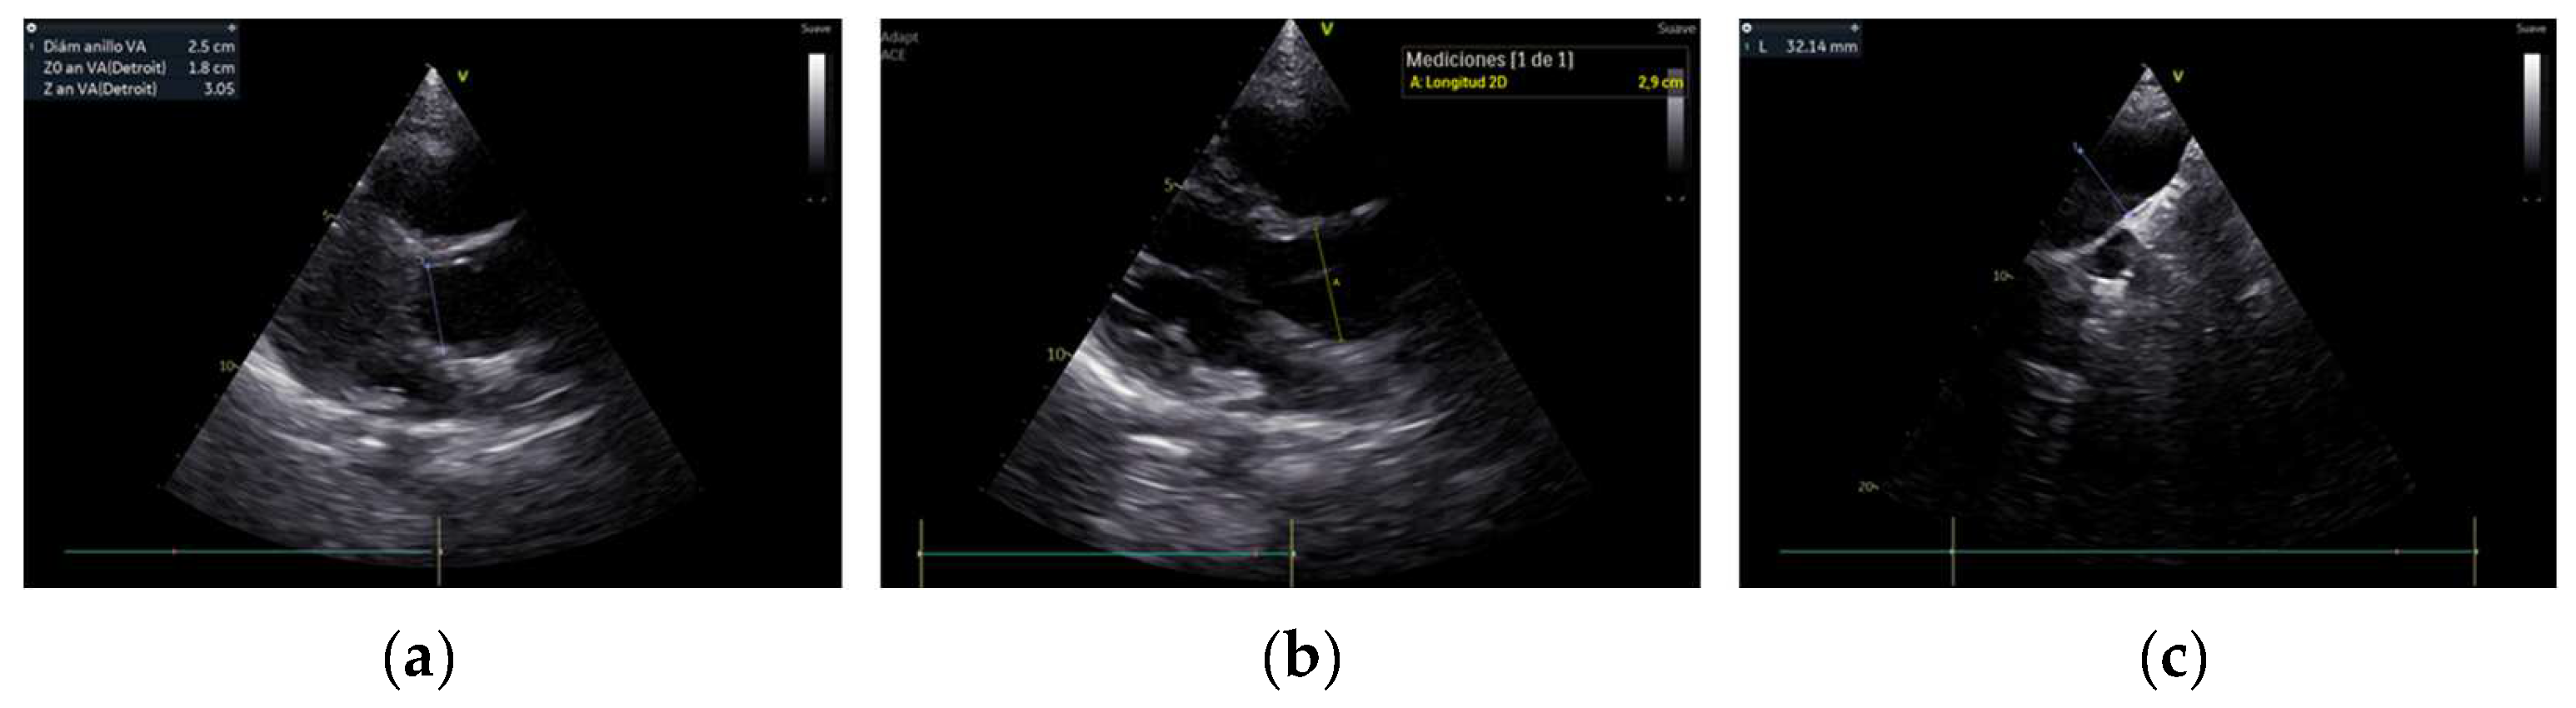

3.2. Echocardiographic Findings and Speckle-Tracking-Echocardiographic Parameters